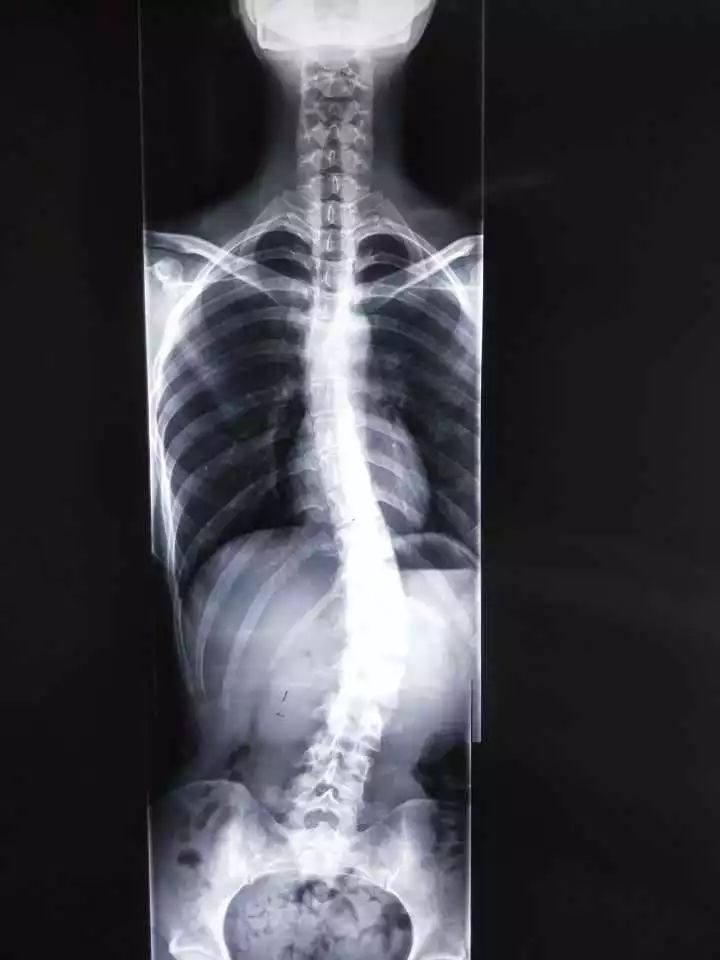

林女士的女儿也是23岁,在上海念大四,也有脊柱侧弯,上衣撩起来,腰部左侧明显比右侧高,X片里,脊柱呈现一个C型。“说是青春期的毛病,现在矫正来不及了,要是开刀,得在脊柱上打钉子,被钉子‘钉着’过一辈子,太遭罪了!”

“ 腰左侧高,脊柱往右边弯了。 ”他再仔细查看了X片,接着往下说,“小姑娘侧弯的度数还是比较厉害的,Cobb角已经超过30°了。”

目前脊柱侧弯测量多选择Cobb角,如果超过10°,就需要引起重视。

国际脊柱侧弯研究学会提出: 应用Cobb角法测量,站立正位X线片的脊柱侧方弯曲,大于10度为脊柱侧弯,大于25度就必须进行支具治疗,而大于40度时就已具备手术指征。